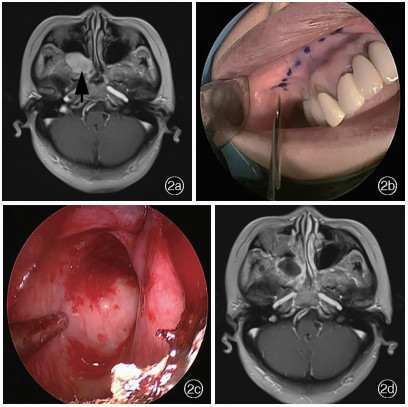

Tabari A , Nasirmohtaram S , Mohammadi HR , Zeinalizadeh M , Sadrehosseini SM . Anterior endoscopic sublabial transmaxillary access to middle cranial base lesions. Head Neck, 2024, 46: 1028- 1042.

doi: 10.1002/hed.27725